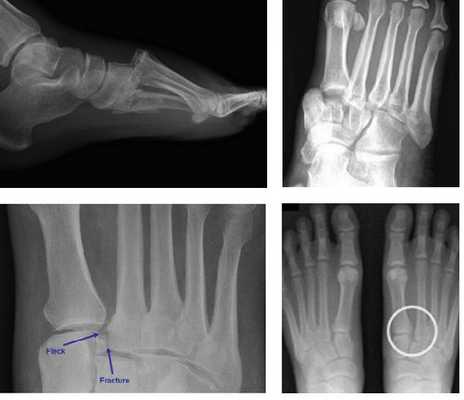

• Рентгенография в передне-задней проекции: смещение плюсневых костей относительно клиновидных костей

• Нормальное расположение данных костей при рентгенографии в передне-задней проекции:

о 1-я плюсневая кость должна располагаться по центру медиальной клиновидной кости

о Медиальный край 2-й плюсневой кости должен находиться на одной линии с медиальным краем промежуточной клиновидной кости

о Латеральный край 3-й плюсневой кости должен находиться на одной линии с латеральным краем латеральной клиновидной кости

о Шиловидный отросток 5-й плюсневой кости должен выходить за латеральный контур кубовидной кости

• Часто выявляются переломы плюсневых костей, клиновидных костей и кубовидной кости

• Рентгенография в боковой проекции: смещение оснований плюсневых костей в тыльную, реже - в подошвенную сторону(Слева) При рентгенографии среднего отдела стопы в передне-задней проекции определяется травма сустава Лисфранка без повреждения 1 -го предплюсне-плюсневого сустава. Следует отметить наличие вывихов 2-го, 3-го, 4-го и 5-го предплюсне-плюсневых суставов и множественных отрывных переломов. Кроме того, выявляется переломовывих медиального ладьевидно-клиновидного сустава.

(Справа) При рентгенографии среднего отдела стопы в передне-задней проекции определяется односторонний вывих сустава Лисфранка: все пять плюсневых костей смещены латерально. Основание пятой плюсневой кости смещено почти до уровня пяточно-кубовидного сустава. Выявляется множество костных фрагментов. (Слева) При рентгенографии среднего отдела стопы в задне передней проекции определяется дивергентный переломовывих сустава Лисфранка: 1-я плюсневая кость смещена медиально, 2-я и 3-я плюсневые кости-латерально. Кроме того, в основании 5-й плюсневой кости выявляются два поперечных перелома.

(Справа) При рентгенографии среднего отдела стопы в передне-задней проекции визуализируется редкий продольный переломовывих сустава Лисфранка. Наблюдается отделение 1-й плюсневой и клиновидной костей от оставшейся части сустава Лисфранка. Также выявляется вколоченный перелом ладьевидной кости.в) Дифференциальная диагностика: